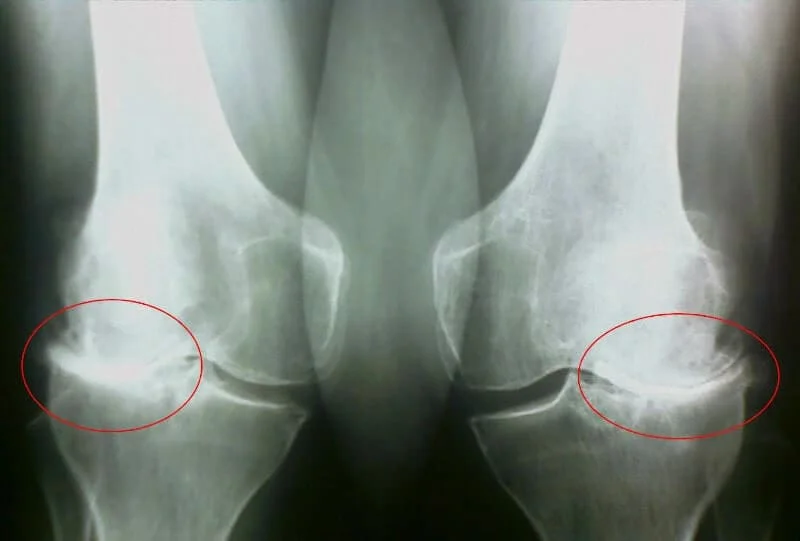

⚠️ Боғимлар Муаммоси?

Боғимлар зирқираб оғриши

Тўхтовсиз, кучли оғриқ ҳисси

Тонгги харакатсизлик

Уйғонгандан кейин қотиб қолиш

Боғимлар қирсиллаши

Харакат қилганда товуш чиқиши

Боғимлар шишиши

Боғим атрофида шиш пайдо бўлиши